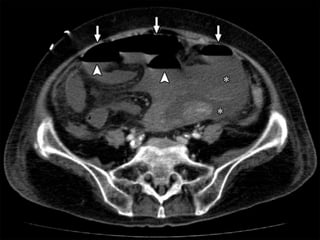

Signs of bowel gangrene:

 Large amount of intraperitoneal fluid

 Gas in the mesenteric / portal vessels

 Intramural gas

 Thinned bowel wall with poor or absent

enhancement

Paper thin bowel wall

White attenuation Grey attenuation

Water target sign Pneumatosis intestinalis

SMV THROMBOSIS

ARTERIAL OCLUSIVE ISCHEMIA VENOUS OCLUSIVE ISCHEMIA

SMA THROMBOSIS SMV THROMBOSIS

NO /SUBTLE BOWEL ENHANCEMENT HYPO/HYPERDENSE BOWEL WALL

THINNED BOWEL WALL (PAPER THIN

BOWEL )

SIGNIFICANT BOWEL WALL

THICKENING

NO MUCOSAL ENHANCEMENT MUCOSAL ENHANCEMENT

BOWEL LOOP DILATATION ONLY AFTER

INFARCTION

DILATED BOWEL LOOPS WITHOUT

LATE STAGES –MESENTERIC FAT

STRANDING,EDEMA/HEMORRHAGES

MARKED FAT STRANDING AND

HEMORRHAGE